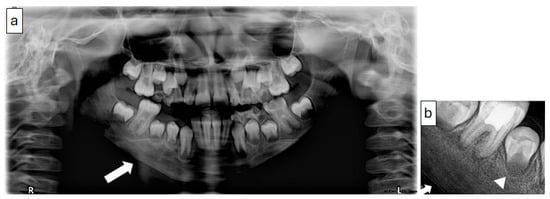

2.3.2. Radiographic Examination

| 3 | 10 | Right mandible (#34–#47, crossing midline) | Granular sclerotic and radiolucent lesion, moth-eaten pattern, layered periosteal reaction | Normal viable bone, sterile | Empirical antibiotics, paracetamol, NSAIDs | CNO confirmed by imaging, CT, and sterile biopsy | NSAIDs only; no need for further escalation | Progressive improvement; under observation |